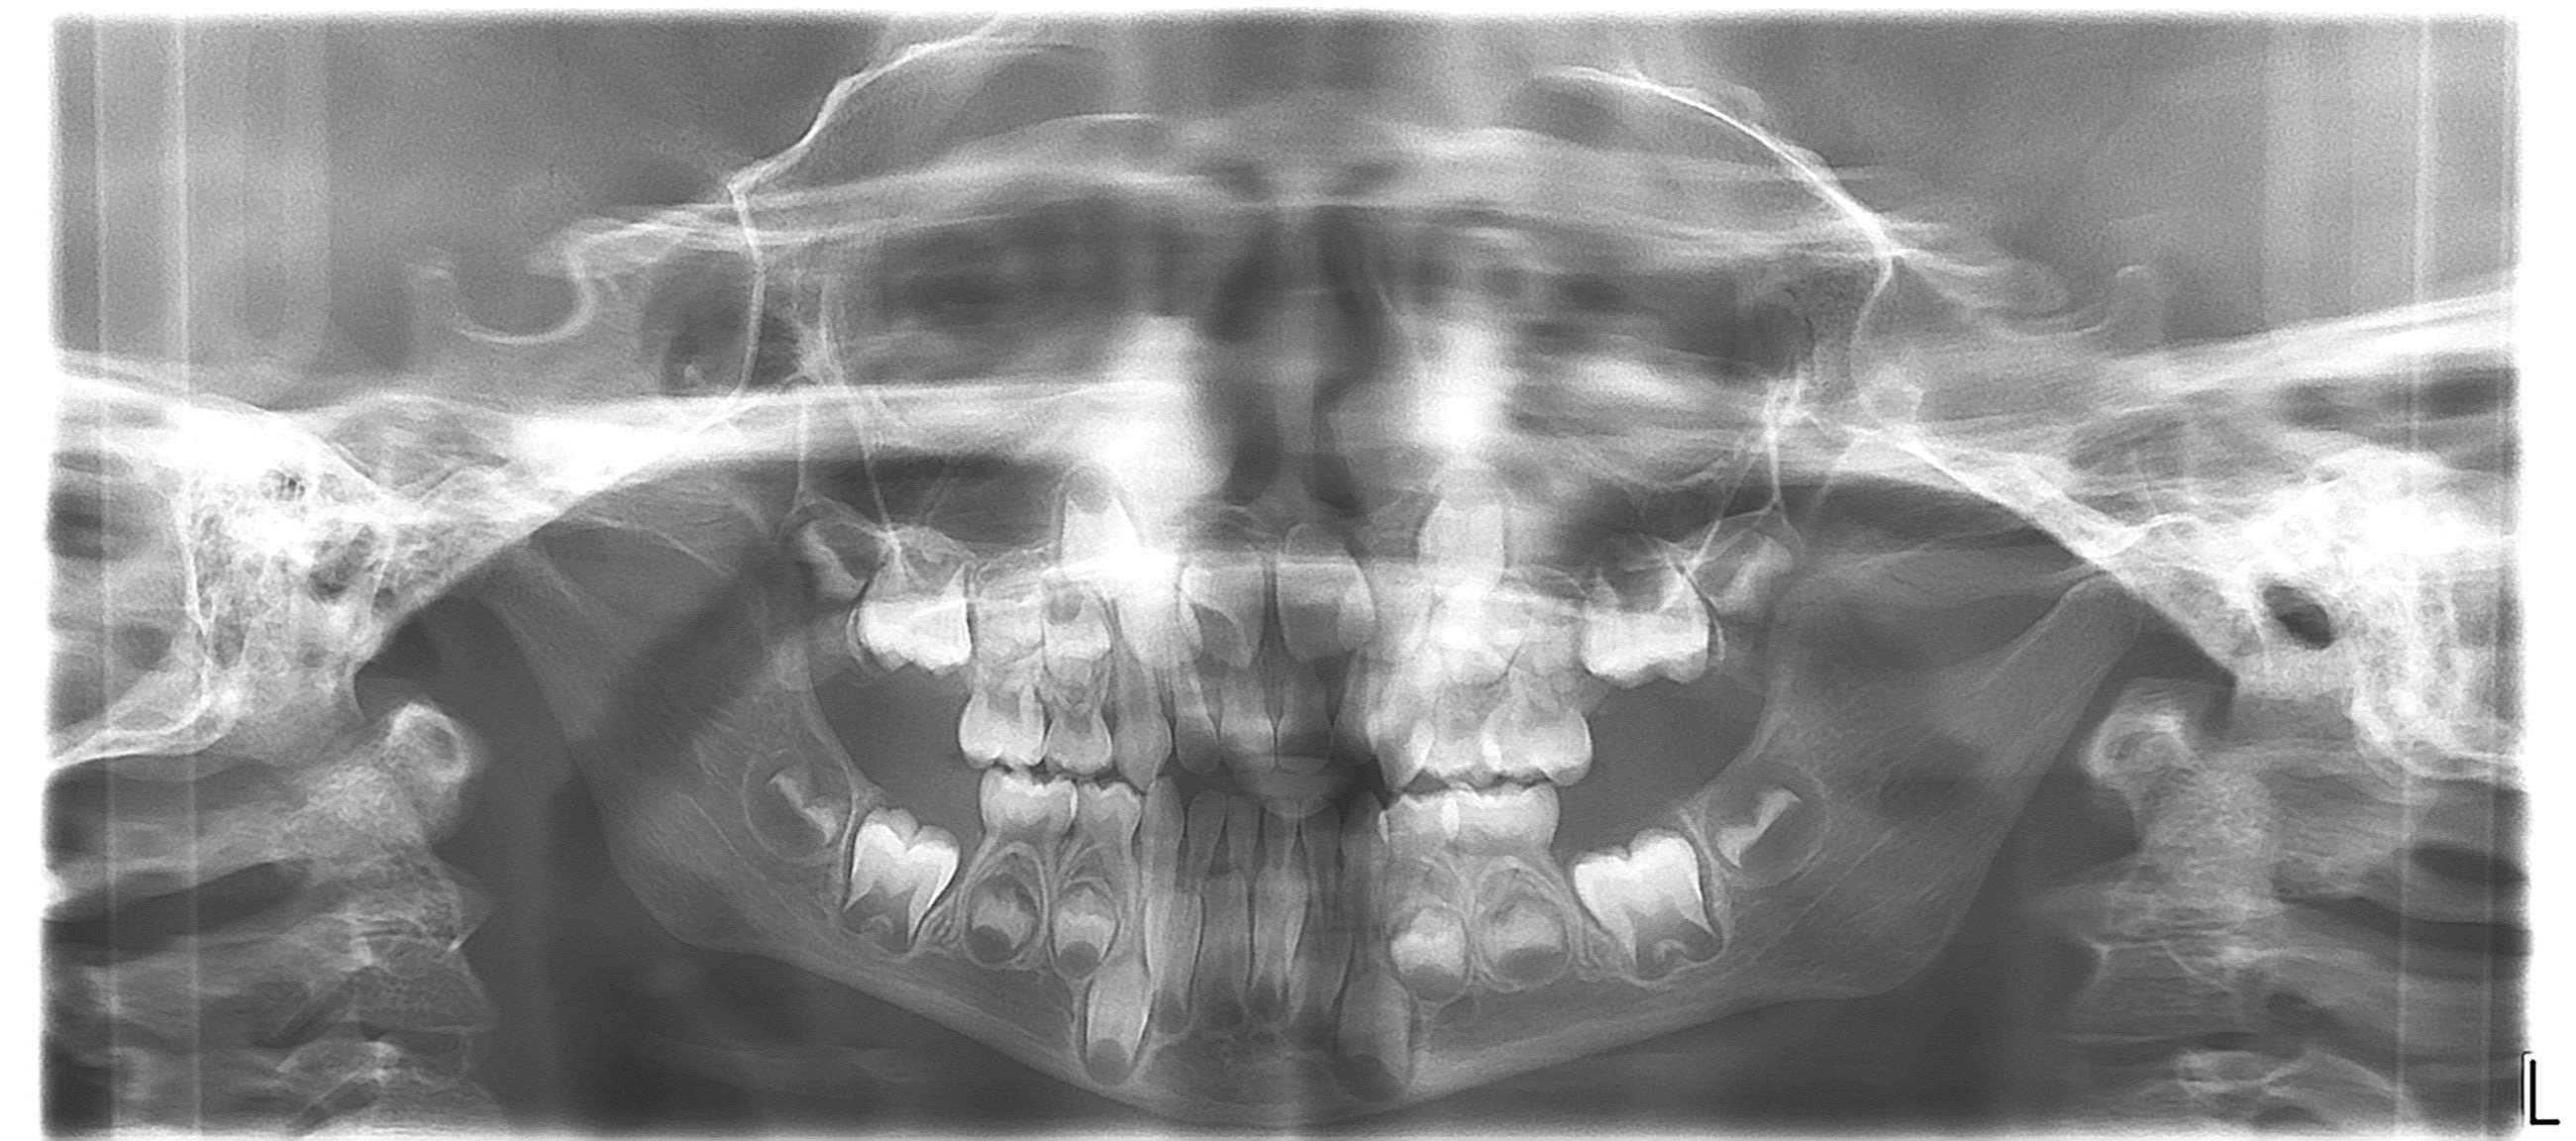

bilan des radiographies début et en cours de traitement

bilan début et en cours de traitement